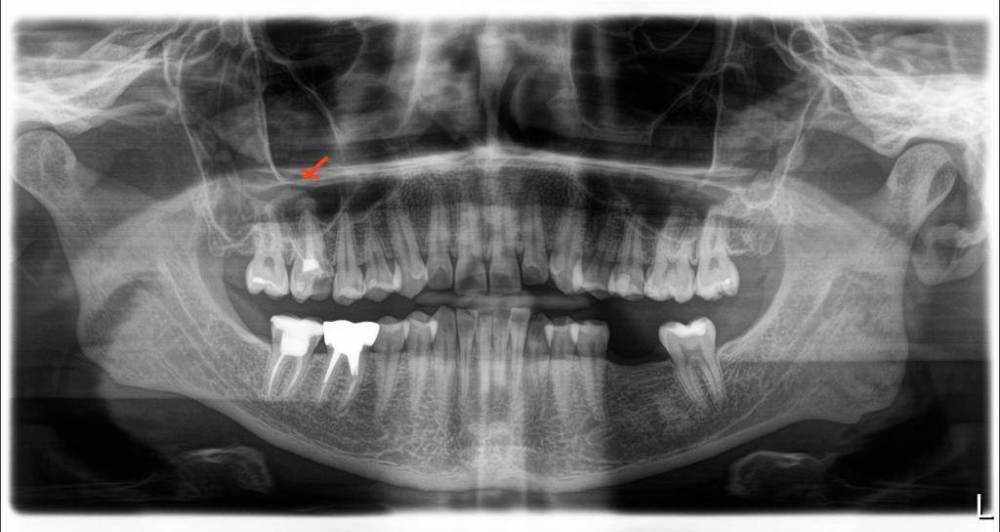

Оксана Бородулина Опубликовано 19 ноября, 2023 Поделиться Опубликовано 19 ноября, 2023 Доброго времени суток! Подскажите, пожалуйста, можно ли спасти зуб? Отмечен красным. Ссылка на комментарий

Bier Опубликовано 20 ноября, 2023 Поделиться Опубликовано 20 ноября, 2023 на первый взгляд - да. нужна ревизия зуба у эндоскописта с микроскопом, потом принятие решения. Ссылка на комментарий

red_butler Опубликовано 20 ноября, 2023 Поделиться Опубликовано 20 ноября, 2023 Здравствуйте, сделайте Кт Ссылка на комментарий